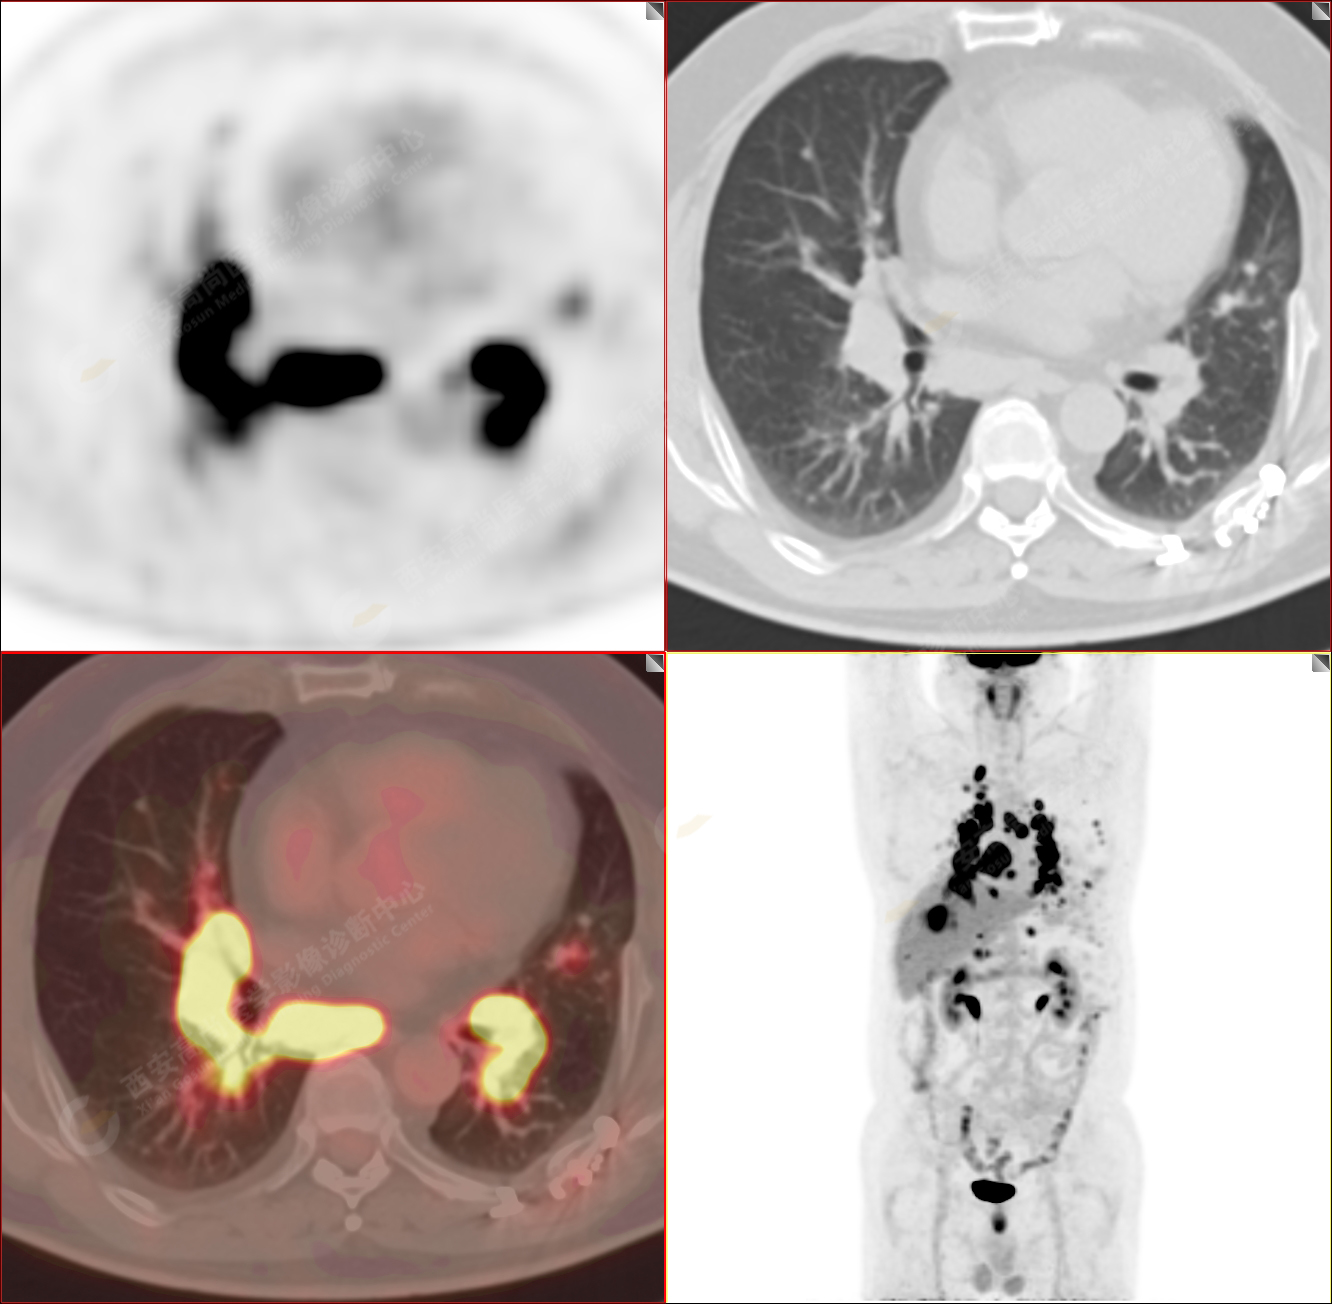

PET/CT-MR診斷結(jié)節(jié)病雙肺及全身多發(fā)淋巴結(jié)廣泛累及1例【西安高尚病例】

男性,53歲,頭暈半月入院,CT發(fā)現(xiàn)肺內(nèi)腫塊,雙肺多發(fā)大小不等實(shí)性及粟粒樣結(jié)節(jié),雙肺門(mén)及縱隔多發(fā)腫大淋巴結(jié)。病程中無(wú)發(fā)熱、胸悶氣及胸部不適。既往:左側(cè)肋骨外傷史。

PET/CT圖像